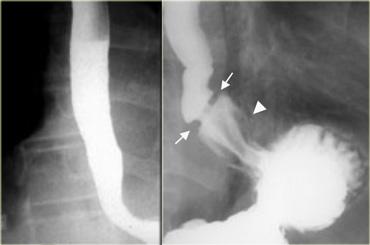

Bên trái là hình ảnh nam bệnh nhân 52 tuổi với triệu chứng nuốt khó từng đợt.

Hình ảnh ngoài cùng bên trái không cho thấy bất thường, tuy nhiên thực quản đoạn xa chưa giãn căng.

Khi thực quản đoạn xa giãn căng, vòng B Schatzki rộng 13 mm (các mũi tên) gây tắc nghẽn từng đợt được hiển thị rõ tại đỉnh của thoát vị hoành (đầu mũi tên).

Bên trái là hình ảnh nam bệnh nhân 71 tuổi với triệu chứng đau ngực sau bữa ăn nhanh.

Khiếm khuyết ngấm thuốc gây tắc nghẽn ở đoạn xa (mũi tên) là một mảnh thịt đã di chuyển vào dạ dày trong quá trình thăm khám.

Hình ảnh thực quản chụp theo dõi cho thấy vòng B Schatzki (các mũi tên) là nguyên nhân gây tắc nghẽn.